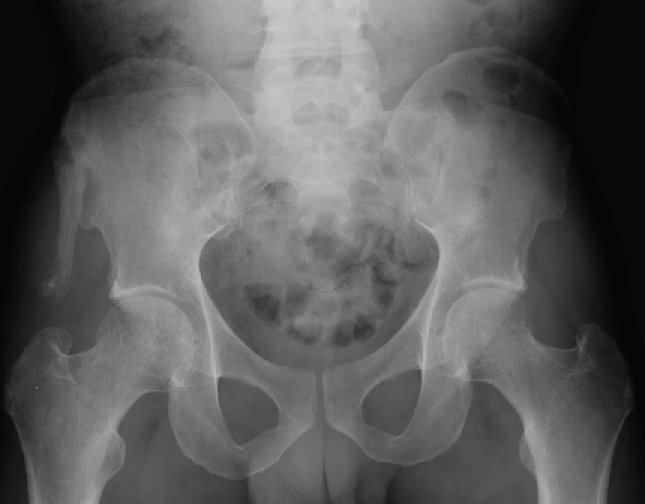

Return to Avulsion Fracture (Pelvis)